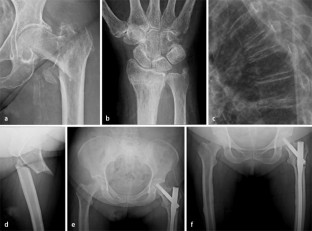

Abb. 3

Zur Ermittlung der Knochendichte stehen 2 State-of-the-art-Verfahren zur Verfügung: „dual energy X-ray absorptiometry“ (DXA) und quantitative Computertomographie (QCT). Für die Diagnostik von Insuffizienzfrakturen stehen Projektionsradiographie, Multidetektorcomputertomographie (MDCT) und Magnetresonanztomographie (MRT) zur Verfügung.

There are two state of the art imaging methods for the quantification of fracture risks: dual energy X-ray absorptiometry (DXA) and quantitative computed tomography (QCT). Radiography, multidetector computed tomography (MDCT) and magnetic resonance imaging (MRI) are suitable for the detection of insufficiency fractures.